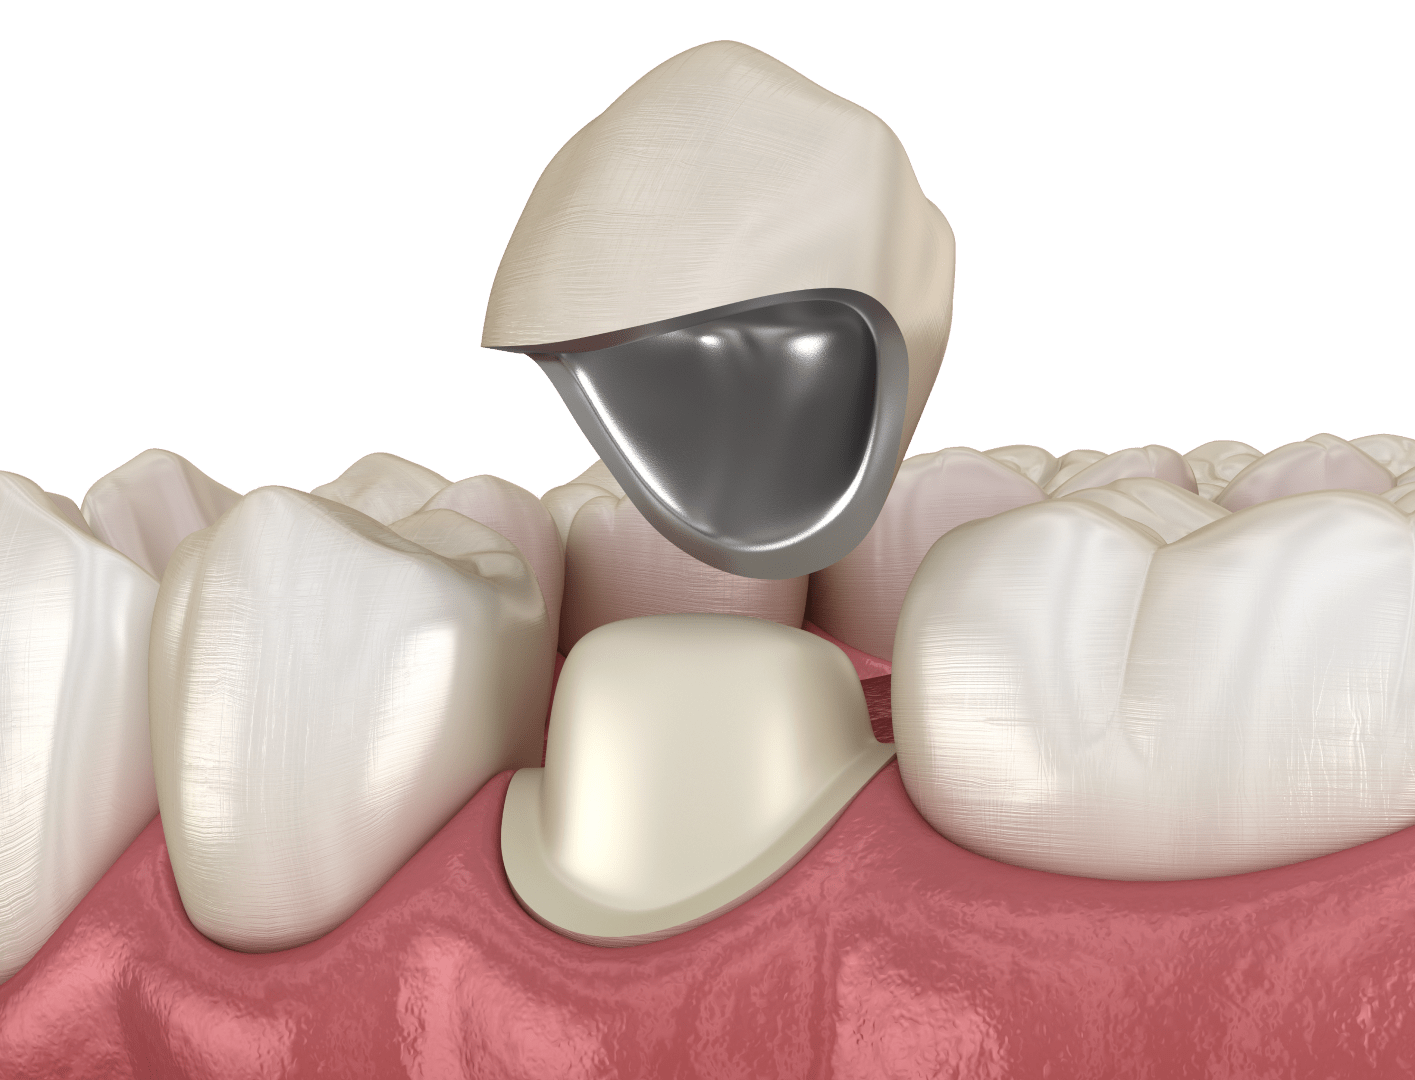

Металокерамічні коронки — це протези, що складаються з міцного металевого каркаса та керамічного покриття. Така конструкція дозволяє відновити анатомічну форму зуба, його жувальну функцію та естетику. Завдяки керамічному шару коронка виглядає максимально природно, тому її зовнішній вигляд майже неможливо відрізнити від натурального зуба.

Металокерамічна коронка — це незнімний зубний протез, який встановлюють на попередньо підготовлений (обточений) зуб або фіксують на зубний імплант у разі відсутності природного кореня. Така конструкція використовується для відновлення форми, функції та естетики сильно пошкоджених або втрачених зубних одиниць.

Коронка з металокераміки має двошарову конструкцію. Основою протеза є міцний металевий каркас, який виготовляють зі спеціальних стоматологічних сплавів, наприклад кобальто-хромового або інших біосумісних матеріалів. Саме каркас надає коронці високу міцність і здатність витримувати значні жувальні навантаження.

Зовнішня частина коронки покривається шаром стоматологічної кераміки. Вона відтворює природний колір, прозорість і форму зубної емалі, завдяки чому конструкція виглядає максимально натурально. Надійне з’єднання металевого каркаса та керамічного покриття досягається під час термічної обробки у зуботехнічній печі, де матеріали поєднуються на молекулярному рівні.